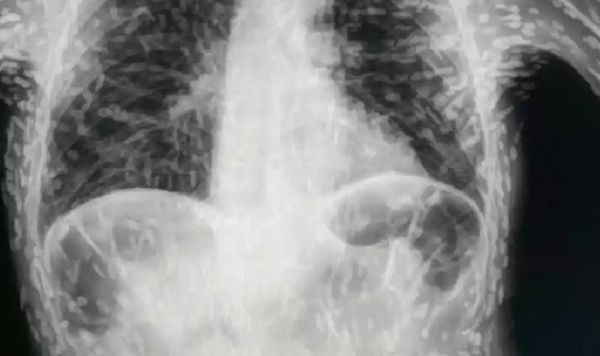

▲患者不停咳嗽,意外發現體內全是蟲卵。(圖/翻攝自Twitter)

巴西壹名患者因為持續咳嗽長達2個多月前去就醫,沒想到醫生檢查發現,他的體內竟然充滿著寄生蟲,所照出的數百個白點都是寄生蟲卵的鈣化殘殼,可怕照片分享在網路後爆紅。

在巴西聖保羅州博圖卡圖(Botucatu)醫院任職的男醫生維克多(Vitor Borin de Souza),上月在推特上分享了壹張X光照,照片中可看到,患者體內充滿各種白點點,原來患者感染了囊蟲病(cysticercosis),是由豬肉絛蟲(Taenia solium)幼體所引發的病症。

維克多表示,患者之所以感染此病,通常是吃了不潔的食物而攝入蟲卵,白色點點其實是幼蟲已經鈣化的包囊,對人體不具威脅,在大多數情況下,患者不需要接受特別治療,除非在頭部與眼部引發致命感染。

維克多表示,若是發現寄生蟲跑到大腦、髓質、眼睛等部位,除了會引發頭痛、腦積水、癲癇等症狀,若沒有及時治療還有可能喪命,為了慎重起見,後來已安排患者前去接受頭部MRI檢查。- 新聞來源於其它媒體,內容不代表本站立場!